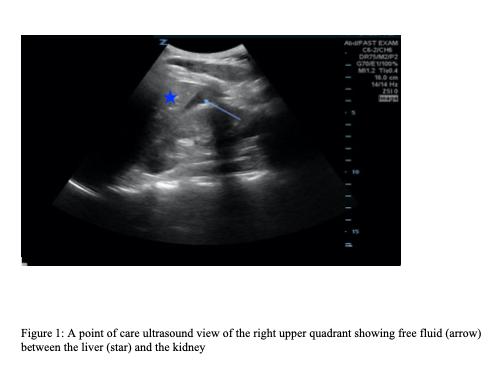

A 36-year-old female with a prior surgical history of hysterectomy without oophorectomy presented to the emergency department with lower abdominal pain. A POCUS revealed free fluid in the right upper quadrant with an unremarkable gallbladder. Subsequently, the pelvic POCUS noted free fluid as well as a heterogeneous structure in the right adnexa. The clinician ordered a serum beta human chorionic gonadotropin level, which was 173.2 international units per milliliter (lU/mL) (negative: < 5m IU/ml). Transvaginal ultrasound revealed a right adnexal echogenic structure with surrounding vascularity and moderate, complex free fluid suggestive of hemorrhage. Given the concern for possible ectopic pregnancy, obstetrics took the patient to the operating room where a right tubal ectopic pregnancy was confirmed.

一名36岁女性,既往有子宫切除术史,未行卵巢切除术,因下腹痛就诊于急诊科。POCUS显示右上腹有游离液体,胆囊无异常。随后,盆腔POCUS发现有游离液体以及右侧附件区有一个不均匀结构。临床医生检测了血清β-人绒毛膜促性腺激素水平,为173.2国际单位/毫升(IU/mL)(阴性:<5mIU/ml)。经阴道超声显示右侧附件区有一个回声结构,周围有血管,并有中度、复杂的游离液体,提示有出血。鉴于可能存在异位妊娠,产科医生将患者送往手术室,术中证实为右侧输卵管异位妊娠。